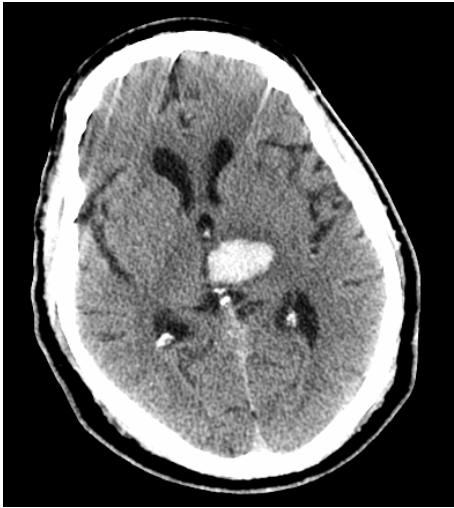

• 61 y/o man with history of poorly controlled HTN did not show up for work.

• His son found him on the floor, confused, having slurred speech, and unable to get up.

• Exam showed dysarthria, moderate right sided weakness, and right sided sensory loss.

• Vitals: 230/135, HR 104, RR 27

• CT is attached

What part of the brain is affected?

Left Thalamus (& Left Internal Capsule)

What type of lesion is this?

Hemorrhagic Stroke (Recall: Hemorrhage is bright on CT!)

What vessel was affected by the lesion?

Small lacunar vessels (Again, think deep structures of the brain for lacunar stroke)

What underlying factors likely caused the lesion?

Hyaline arteriolosclerosis & Hypertension

**Case 8 Q# 1 of 3** * 19 y/o man collapsed playing basketball. He was having a seizure consisting of right arm shaking and then fell to the ground without protecting himself. * On arrival noted to have weakness on his right side, reactive pupils, positive corneals and cough. Not following commands or moving spontaneously. * Vitals: 220/120, HR 45, RR 12 (intubated) * CT is attached What about the CT helps you **rule out** contusion secondary to his fall as the cause of his lesion?

The lesion is **located** in the middle of the cortex. Contusion damage typically occurs around the **frontal pole, occipital pole, or temportal tips** of the brain

**Case 8 Q# 2 of 3** * 19 y/o man collapsed playing basketball. He was having a seizure consisting of right arm shaking and then fell to the ground without protecting himself. * On arrival noted to have weakness on his right side, reactive pupils, positive corneals and cough. Not following commands or moving spontaneously. * Vitals: 220/120, HR 45, RR 12 (intubated) * CT is attached Looking at his CT, what is the underlying brain lesion that has now ruptured to cause his seizure?

Arteriovenous malformation (AVM)

**Case 8 Q# 3 of 3** * 19 y/o man collapsed playing basketball. He was having a seizure consisting of right arm shaking and then fell to the ground without protecting himself. * On arrival noted to have weakness on his right side, reactive pupils, positive corneals and cough. Not following commands or moving spontaneously. * Vitals: 220/120, HR 45, RR 12 (intubated) * CT is attached What further brain injury is this man at imminent risk for? How can you tell?

**Brain Herniation**. **Extreme HTN + low HR = Cushing Reflex**, which is noted in patients with increased ICP and can suggest imminent herniation.